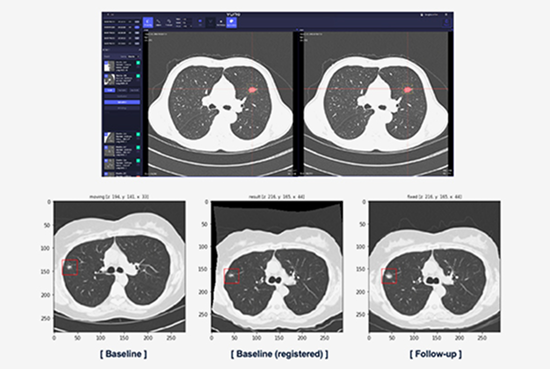

• Provides baseline scans and follow-up data for nodule growth assessment

• Can match the baseline scan and follow-up scan pixel to pixel